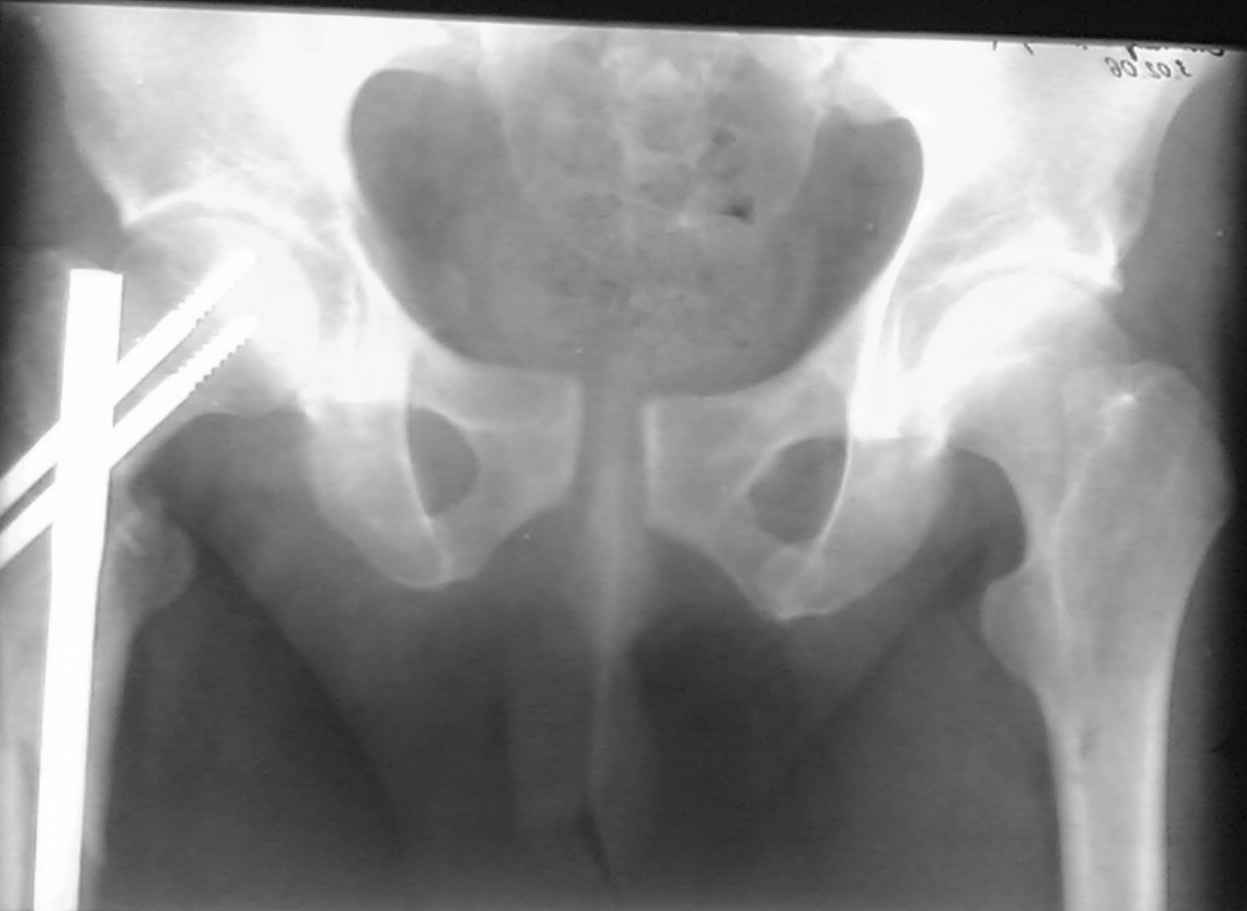

Re: разрыв лонного сочленения

ПЕРЕСМАТРИВАЛ РАЗНЫЕ СНИМКИ И НАШЕЛ НА ЭТУ ТЕМУ ФОРУМА СНИМОК. БОЛЬНОЙ БЫЛ ПРООПЕРИРОВАН НА ПРАВОЕ БЕДРО ПОСЛЕ ЧЕГО СДЕЛАН ТАЗ В ЦЕЛОМ. ВОТ ЧТО НАШЛОСЬ.

КАКОЕ ВАШЕ МНЕНИЕ О ТАКТИКЕ.

ДУМАЮ ПРОШЛО ОКОЛО 10 ДНЕЙ.